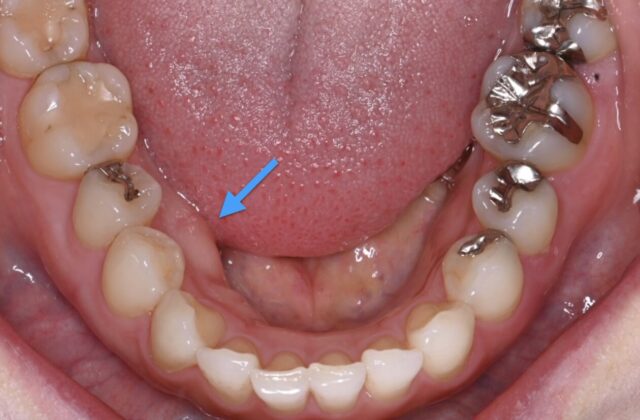

当院は虫歯治療や入れ歯治療にくわえて、歯科会をリードする米国で研鑽を積んだ米国専門医がおこなう歯周病治療、インプラント治療を得意としています。日本では多くの患者様が歯周病を抱えており、高度な治療へのニーズを感じていました。そのため当院の専門医は、より先進的な治療が行われている米国で歯周病とインプラント治療に特化して学び、現地で多くの症例を経験してきました。

痛みに配慮した施術

また歯周病で失われた歯を取り戻すためのインプラント治療も得意としております。米国では歯の周りの骨の再生を得意とする歯周病専門医がインプラント治療を行うため、インプラントに関しても正統で専門的な教育を受けています。